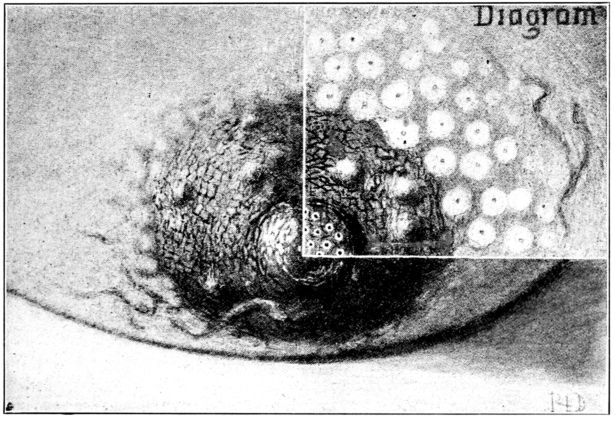

| 18. | Diagram of segmenting rabbit’s ovum | 65 |

| 19. | Ovum about 13 days old embedded in the decidua | 66 |